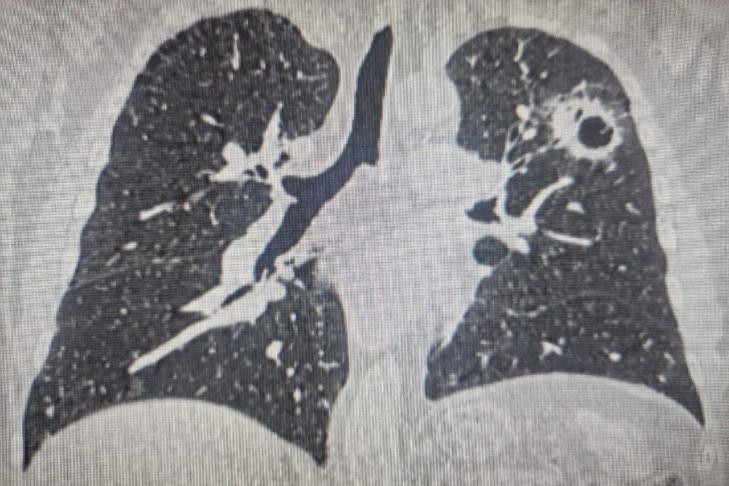

Первая онкологическая операция у пациента, проведенная три года назад, касалась центрального рака правого легкого. Вместо полного удаления легкого, врачи выполнили органосохраняющую операцию – бронхоангиопластическую верхнюю лобэктомию. Это позволило удалить пораженную часть легкого вместе с бронхами и сосудами, сохранив при этом две трети органа. Это стало возможным благодаря предоперационной химиоиммунотерапии, уменьшившей опухоль.

Через год у пациента был вновь диагностирован рак, но уже в левом легком. Эта локализация была обнаружена на очень ранней стадии благодаря регулярному наблюдению. Как пояснил заведующий торакальным отделением № 3 Вадим Козлов, возможность оперировать второе легкое стала реальной только потому, что первое было сохранено. «Технически выполнить операцию на единственном легком невозможно. Если мы его отключим, то дышать пациенту будет нечем», – отметил врач. Удаление сегмента второго легкого уже проводилось эндоскопически.